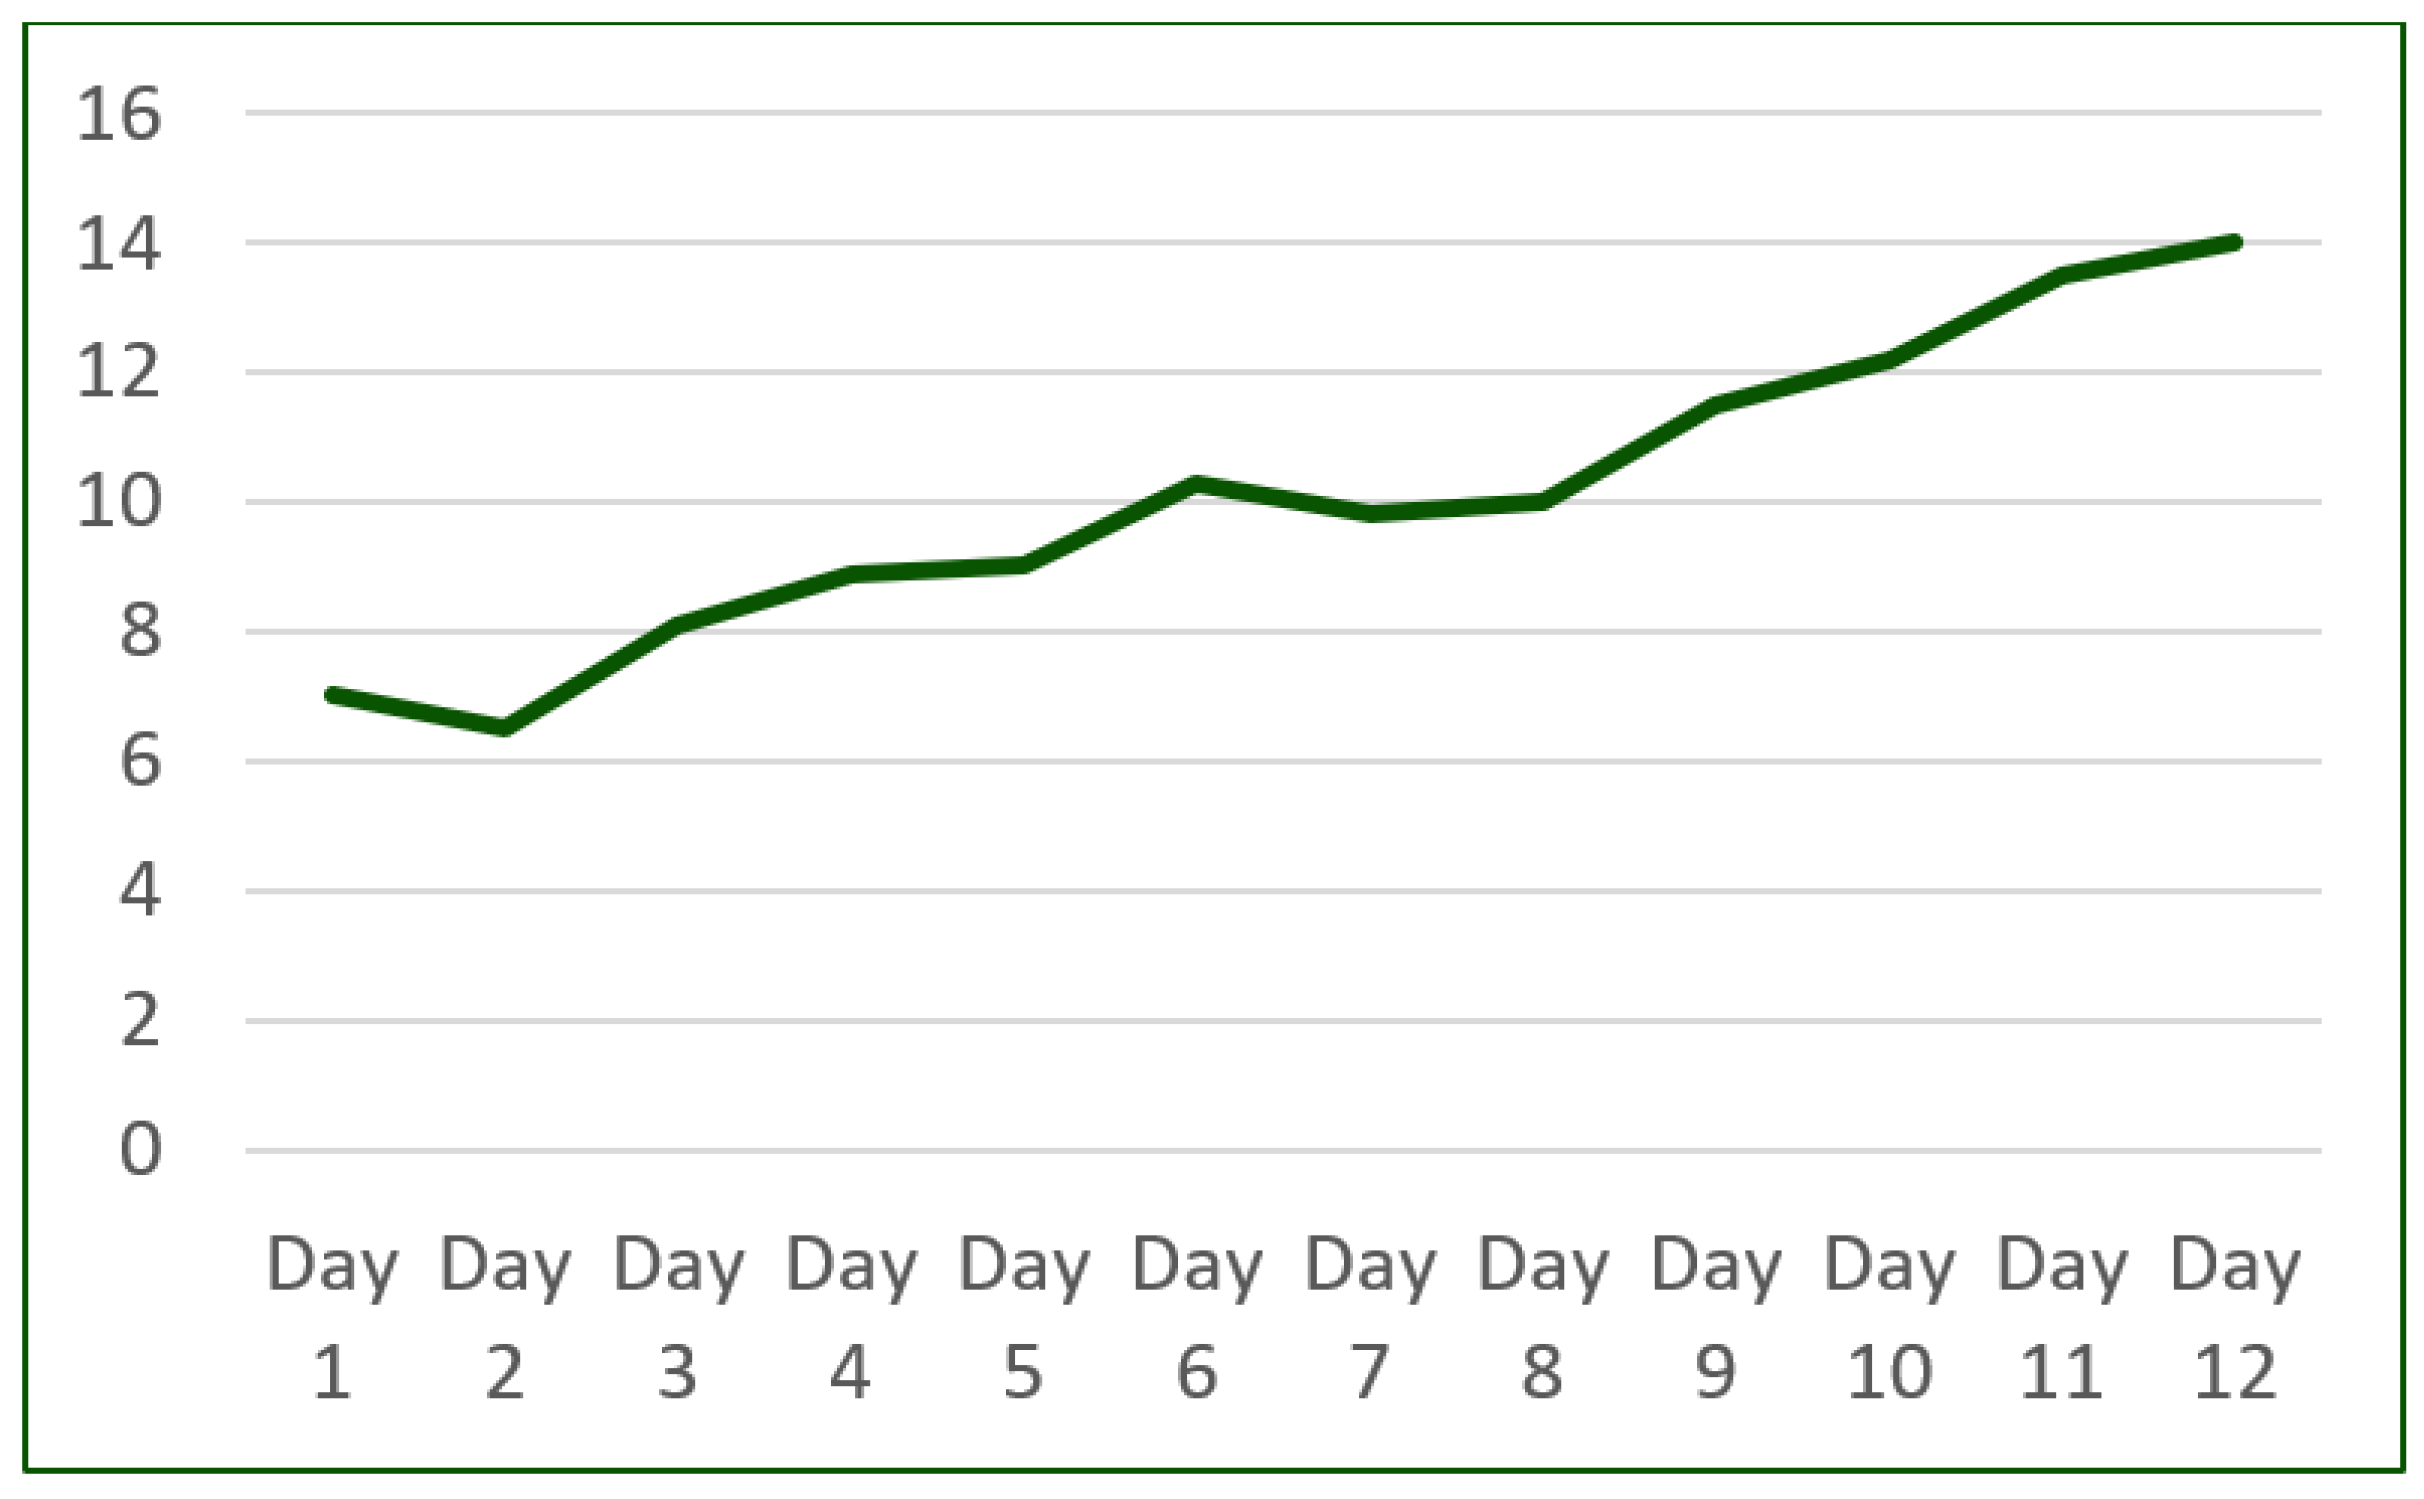

2. Detailed Case Description